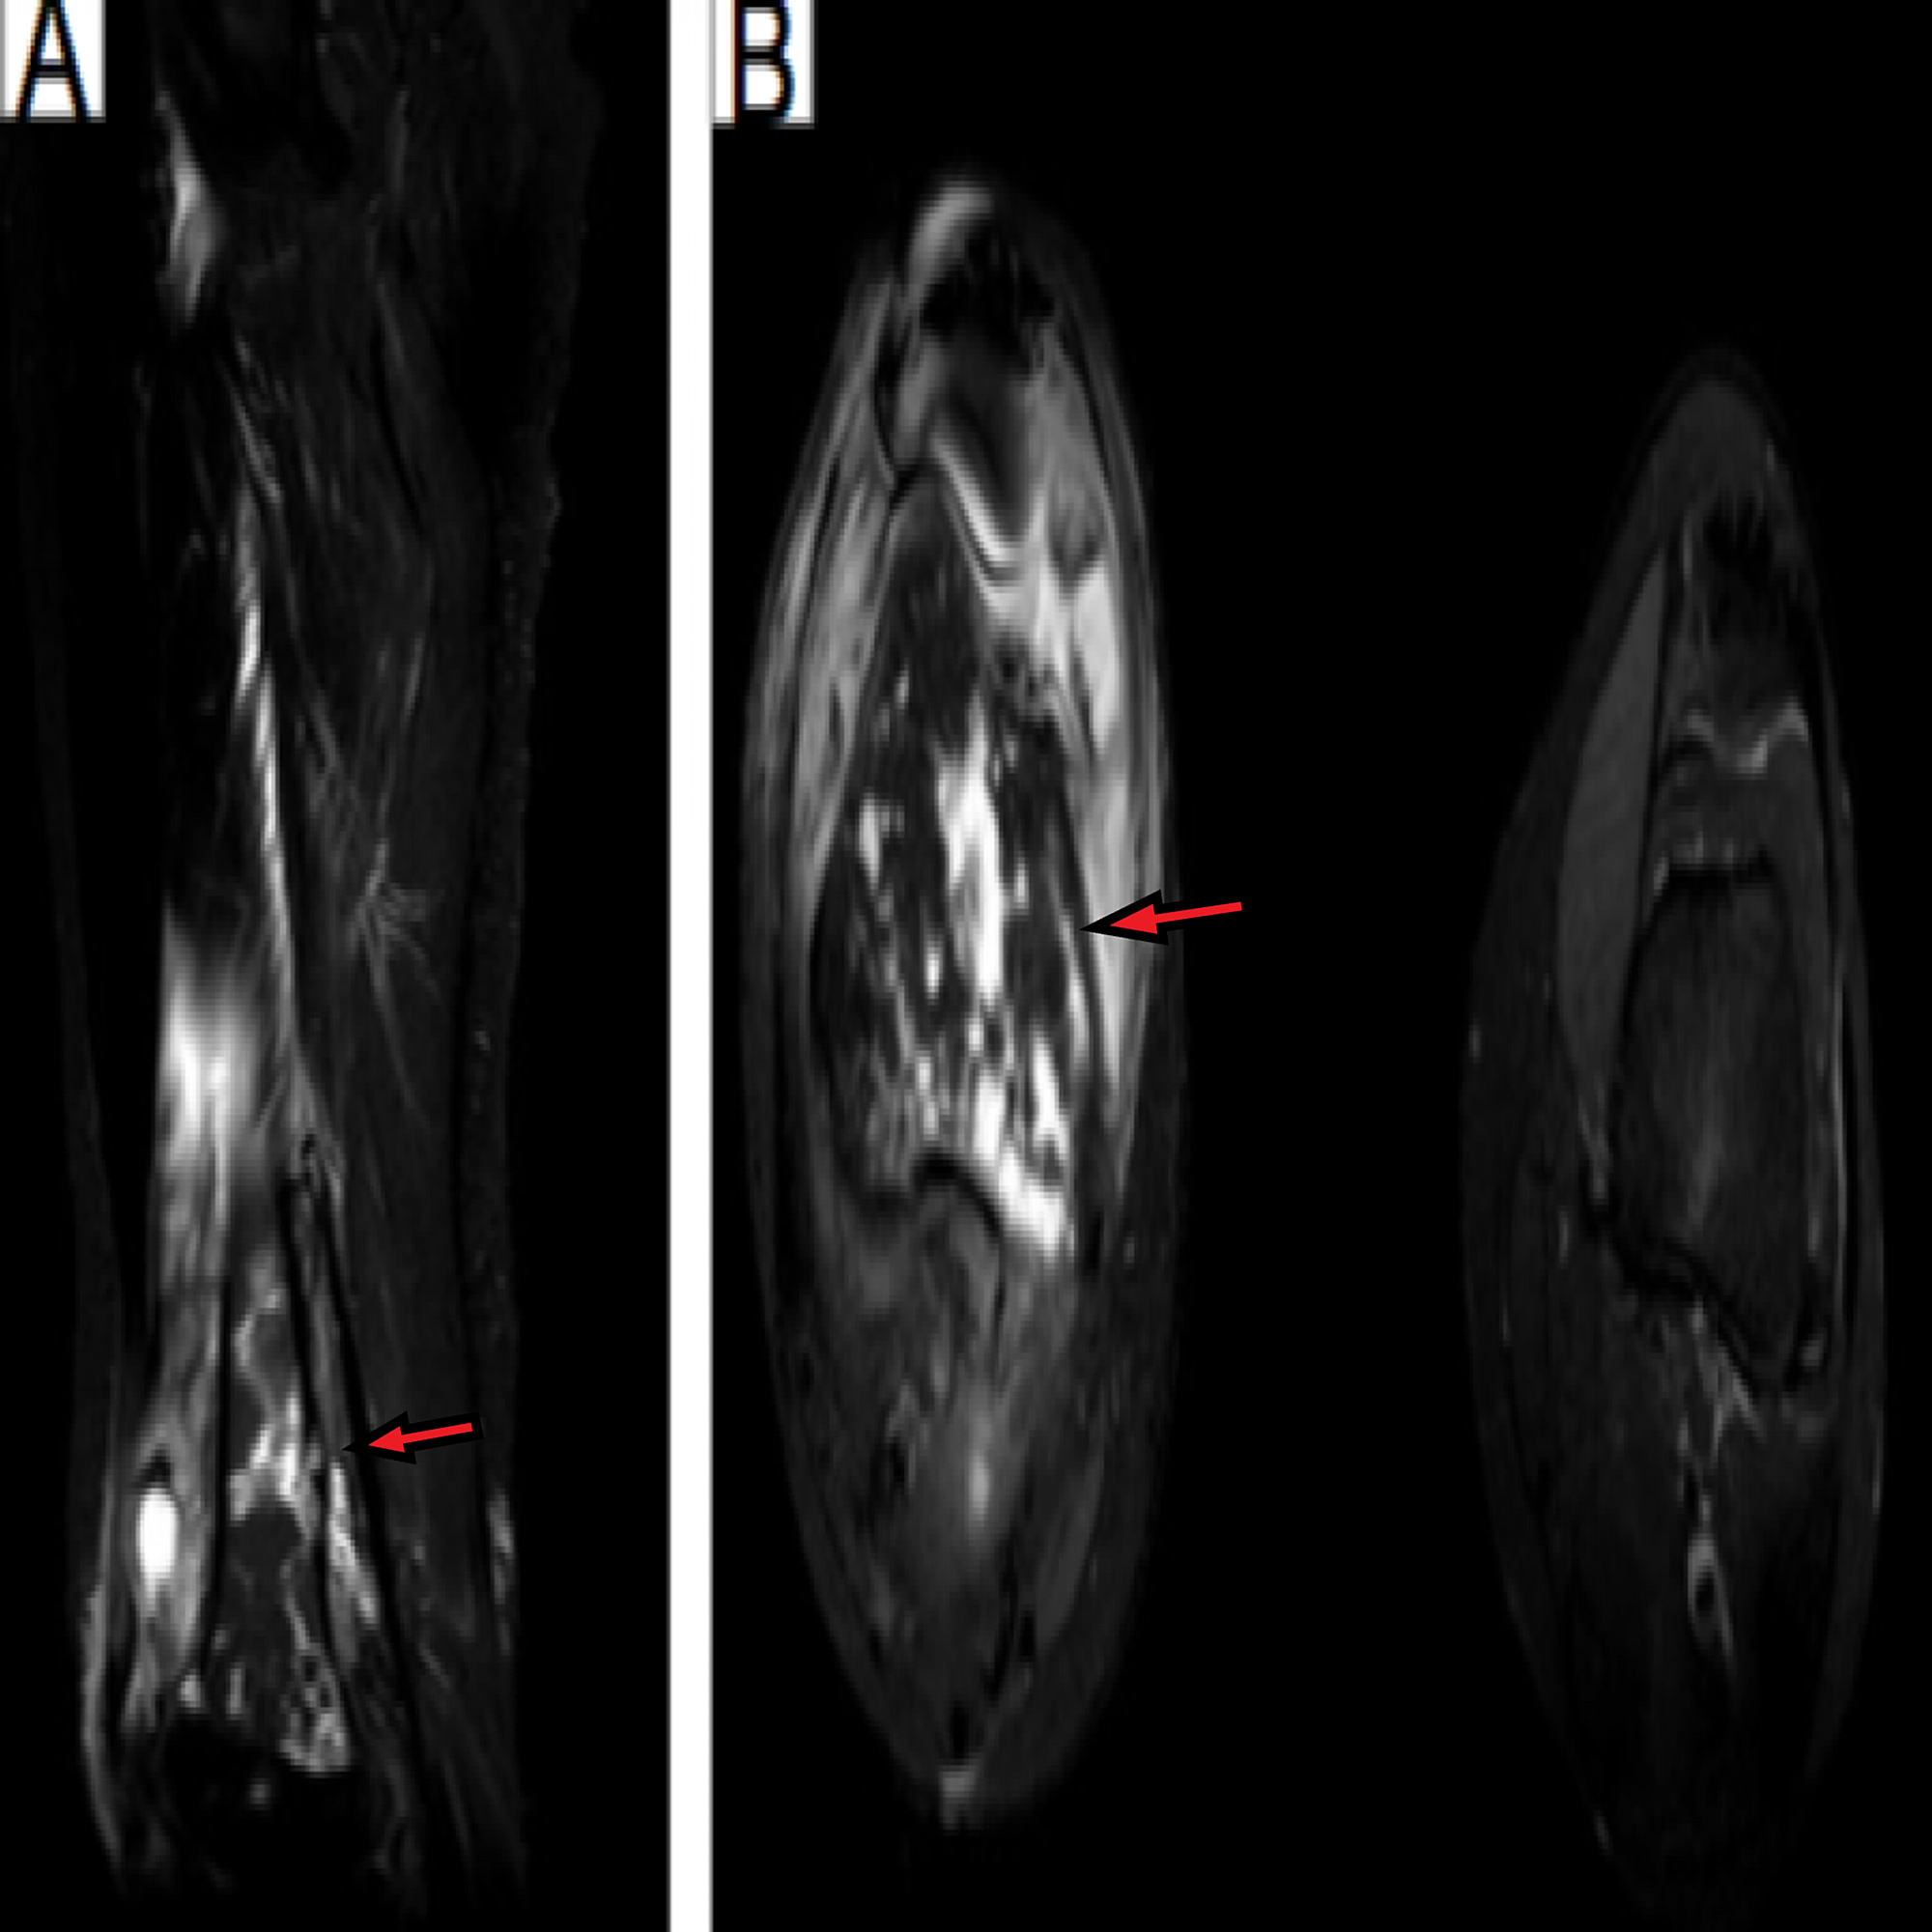

X-ray of the right knee showed lytic lesions; there were multiple cortically based ill-defined lytic lesions of the distal femoral metadiaphysis with surrounding reactive sclerosis (Figure 1). The most proximal lesion was eccentrically located and demonstrated cortical thinning with questionable cortical breakthrough.